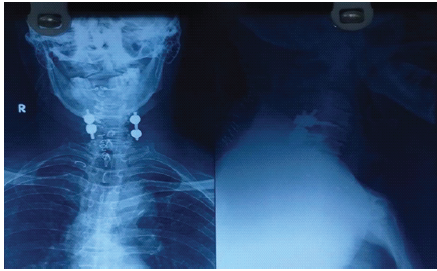

Sensory examination showed reduced sensation over the upper-limb dermatomes (C5–T1), whereas all sensations were preserved in the lower-limb dermatomes (L2–S1). Sacral sensory sparing was present, and the bulbocavernosus reflex was intact, confirming an incomplete injury. Deep tendon reflexes and muscle tone were normal. The patient was classified as ASIA impairment scale grade D, consistent with CCS. The patient presented with quadriparesis, with upper limb weakness more pronounced than lower limbs and reduced motor power and sensation in the upper limbs (Left > Right). The findings are suggestive of CCS. A plain radiograph of the cervical spine showed C5–C6 fracture dislocation (Fig. 2).

Figure 2: Cervical spine X-ray showing C5–C6 fracture dislocation